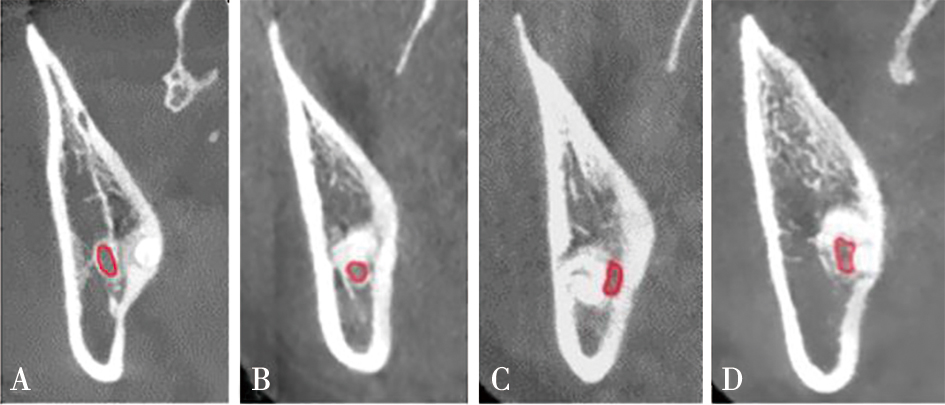

| 下颌管形态(CBCT) | 圆形/卵圆形 | 2 014 | (88.02%) | 274 | (11.98%) | <0.0001* | |

| 狭窄型 | 82 | (7.45%) | 1 019 | (92.55%) | |||

| 下颌管形态(CBCT) | 圆形/卵圆形 | 2 014(88.02%) | 274(11.98%) | ||

| 狭窄型 | 82(7.45%) | 1 019(92.55%) | <0.000 1* | 60.615(46.408,70.181) | |